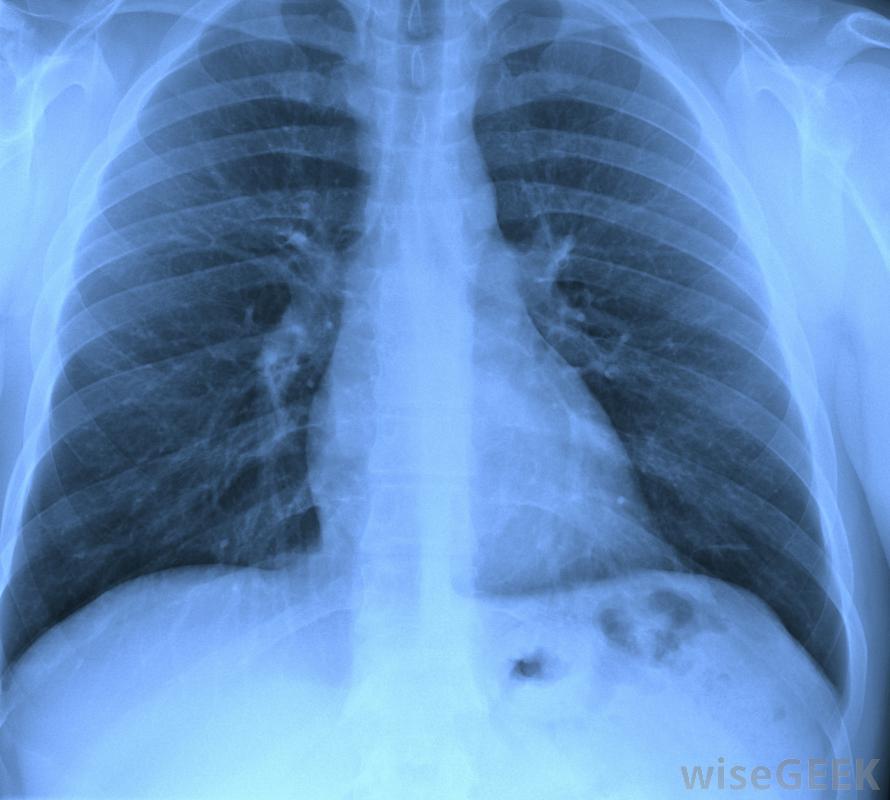

异烟肼与一种或多种药物联合使用时,对结核病最有效,如果病人有暴露的积极迹象,但肺部x光片清晰,结核病的异烟肼可用于积极的联合治疗,初期疗程短,以尽可能多地杀灭细菌。后续治疗可消除残留。在这一治疗过程中,患者需要定期检查以监测肝脏功能检查活动性肺结核正在发展的迹象,并评估其他副作用。活动性肺结核患者也可以使用异烟肼作为联合药物治疗的一部分对他们来说,这种药物可以杀死细菌来抑制感染,并有助于控制疾病的传播。在这种情况下,使用异烟肼治疗结核病的人也需要进行监测,以确保药物安全有效。如果他们出现副作用,其他药物也可以换成联合疗法,从一个新的角度对结核杆菌进行攻击。这是很重要的,要按照指示服用,这样它才能最有效。至少应该在饭前半小时或饭后两小时服用,这样身体才有时间充分吸收它。异烟肼治疗结核病不应与减少胃酸和刺激的药物同时服用,因为这些药物也会干扰吸收,降低药效。如果患者有严重的肝功能不全,患者可能无法服用药物,并且在使用时不应饮酒,因为这可能会损害肝脏。